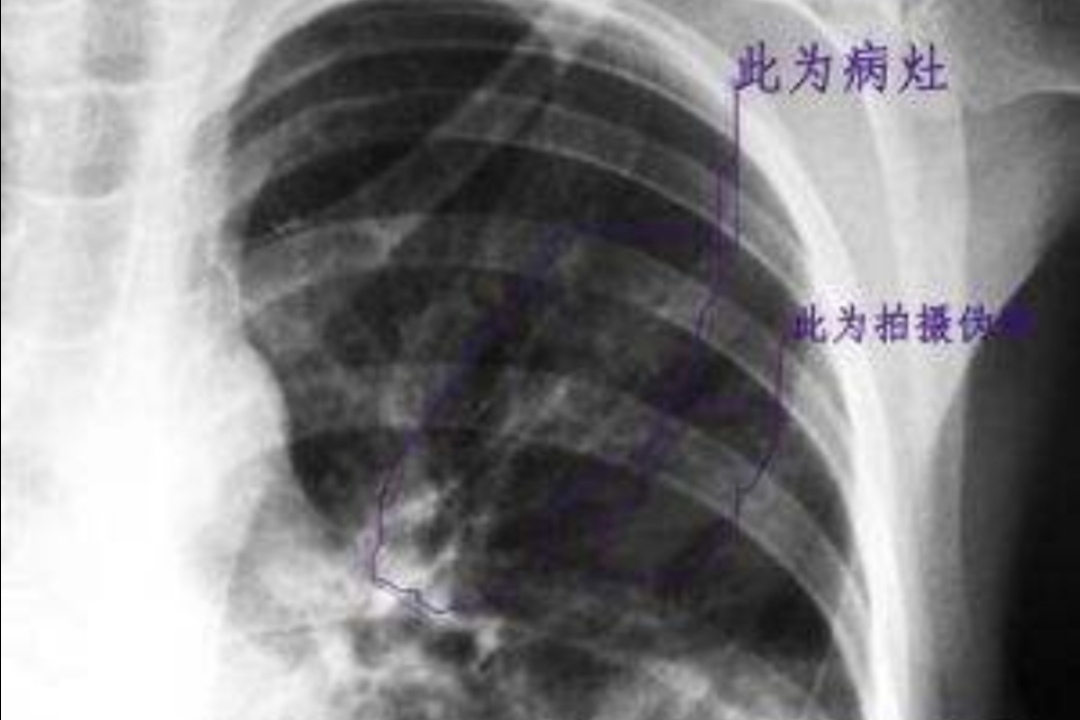

⑤肺部体征少,可有呼吸音减低,病程后期可出现湿性啰音。

⑥肺部体征与症状以及影像学表现不一致是肺炎支原体肺炎的特征。